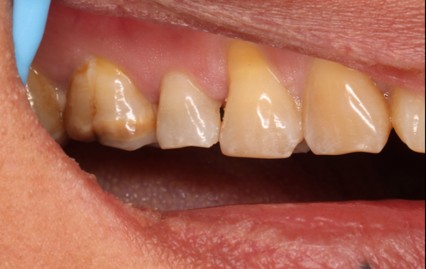

June 20, 2025: The patient's chief complaint is that endodontic treatment was performed on the right maxillary posterior tooth abroad, and a deep carious lesion has been recently detected, requiring restoration. The following are the intraoral photographs taken upon the patient's first visit: a large carious lesion is visible on the occlusal surface of tooth 15 (FDI numbering), with only the buccal wall remaining. Percussion test and cold-hot stimulation test showed no response, and yellow obturation material is visible at the root canal orifices.